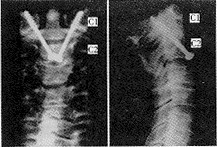

扪及寰椎前结节,沿椎体前正中线切开C1~C3椎前筋膜,骨膜下剥离,切除少量C2~3椎间盘前部,显露枢椎椎体前下缘。于前下缘中点两侧各1mm处,以3.2mm钻头(使用带20°倾斜角的微型电钻),分别按术前计划中制定的螺钉置入角度,向外、向后钻入,经寰枢关节内侧份进入寰椎侧块,至侧块上关节面骨皮质下停止(图3)。测深器测出钉道的全长及其分别在枢椎椎体和寰椎侧块中的长度,选择恰当长度的直径为3.5mm的部分螺纹松质骨螺钉拧入。注意使螺纹全部拧入侧块中,应用拉力螺钉原则,在寰枢关节之间产生加压作用。取出整段颈椎,摄正侧位片(图4)。

图4 手术模型术后正侧位X线片

在17例34侧标本中共置入34枚螺钉,分别测量记录术前计划的角度、螺钉轨道的实际角度及螺钉与椎动脉间距离。术前计划内界角为18°±1.4°,外界角为33°±3.7°,后界角为39°±4.1°。外偏标准角为26°±2.9°,实际外偏角24°±3.5°,两者之间双侧t检验显示两样本均数无显著性差异(P>0.1)。后倾标准角为24°±2.0°,实际后倾角为27°±4.0°,两者无显著性差异(P>0.05),说明手术操作能达到术前计划的要求。

在三个层面的横断面上,螺钉与椎动脉间的距离见附表。以断面C中椎动脉与螺钉之间距离最近,为6±1.4mm,其中1枚螺钉距椎动脉3.5mm,其余33枚距离均大于4mm,无椎动脉及脊髓损伤。2枚螺钉穿入枕颈关节,关节损伤率为5.9%。